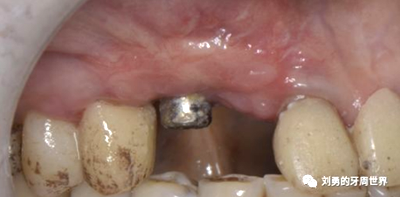

下面這個是我使用國產(chǎn)的替代品的病例:

可見右上前牙植體頰側(cè)無附著齦

為了減少取瓣大小,從上腭取厚一點(diǎn)的齦瓣,然后用刀片平行于表皮表面將齦瓣片切成兩個厚度一致的齦瓣,然后進(jìn)行移植,這樣切成的兩個齦瓣一個有表皮,一個沒有表皮是單純的結(jié)締組織。如此的片切可以使齦瓣變成雙倍的大小使用,減少了供區(qū)的取瓣面積。